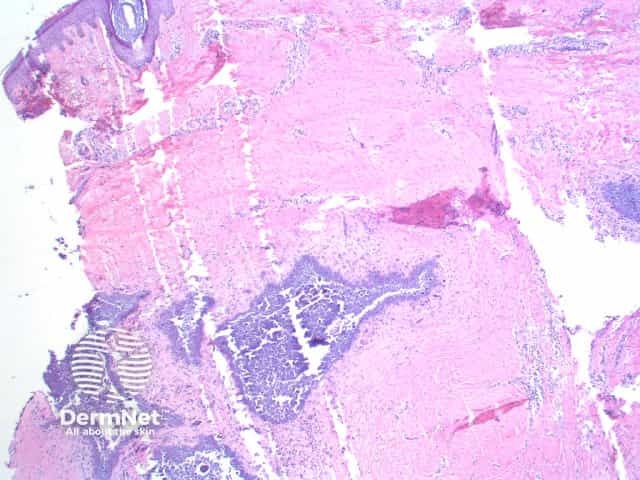

There are irregular deposits of intensely basophilic acellular material in the dermis and subcutaneous tissue (figure 1). The basophilia is so strong that the appearance is of a deep purple (figures 2, 3). The deposits are typically well circumscribed, with a thin rim of eosinophilic hyalinisation and frequently a host giant cell reaction.

Artefactual lines form in the calcification and surrounding tissue due to shatter with cutting (figure 1).

Figure 1